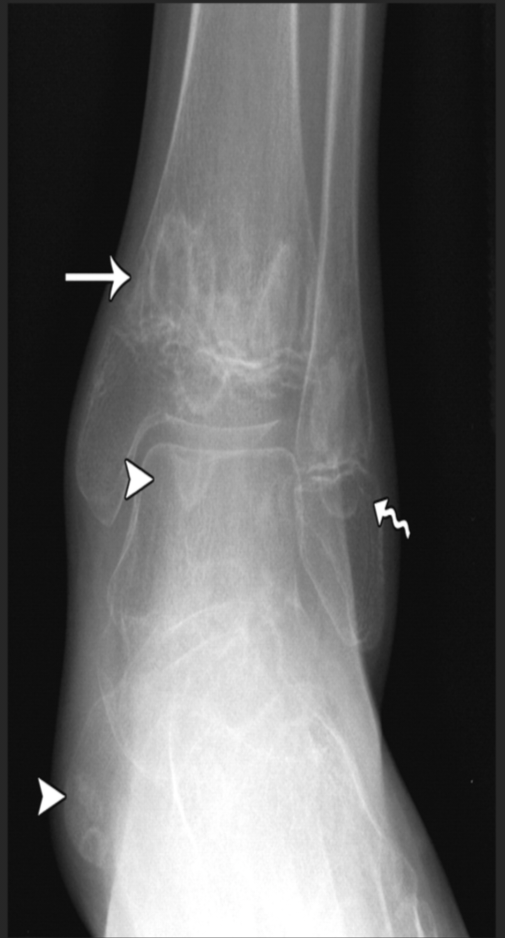

图D 踝部多发溶骨改变

X线:早期可正常,后期可见溶骨性破坏、骨质硬化或骨膜反应。

MRI(金标准):T2加权像高信号(骨髓水肿),增强后强化,可发现早期无症状病灶。

2.典型的影像学表现(特别是STIR MRI提示骨髓水肿+/-,骨膨胀,骨溶解和骨膜反应,或平片提示同时存在骨溶解、骨硬化和新生骨形成)。